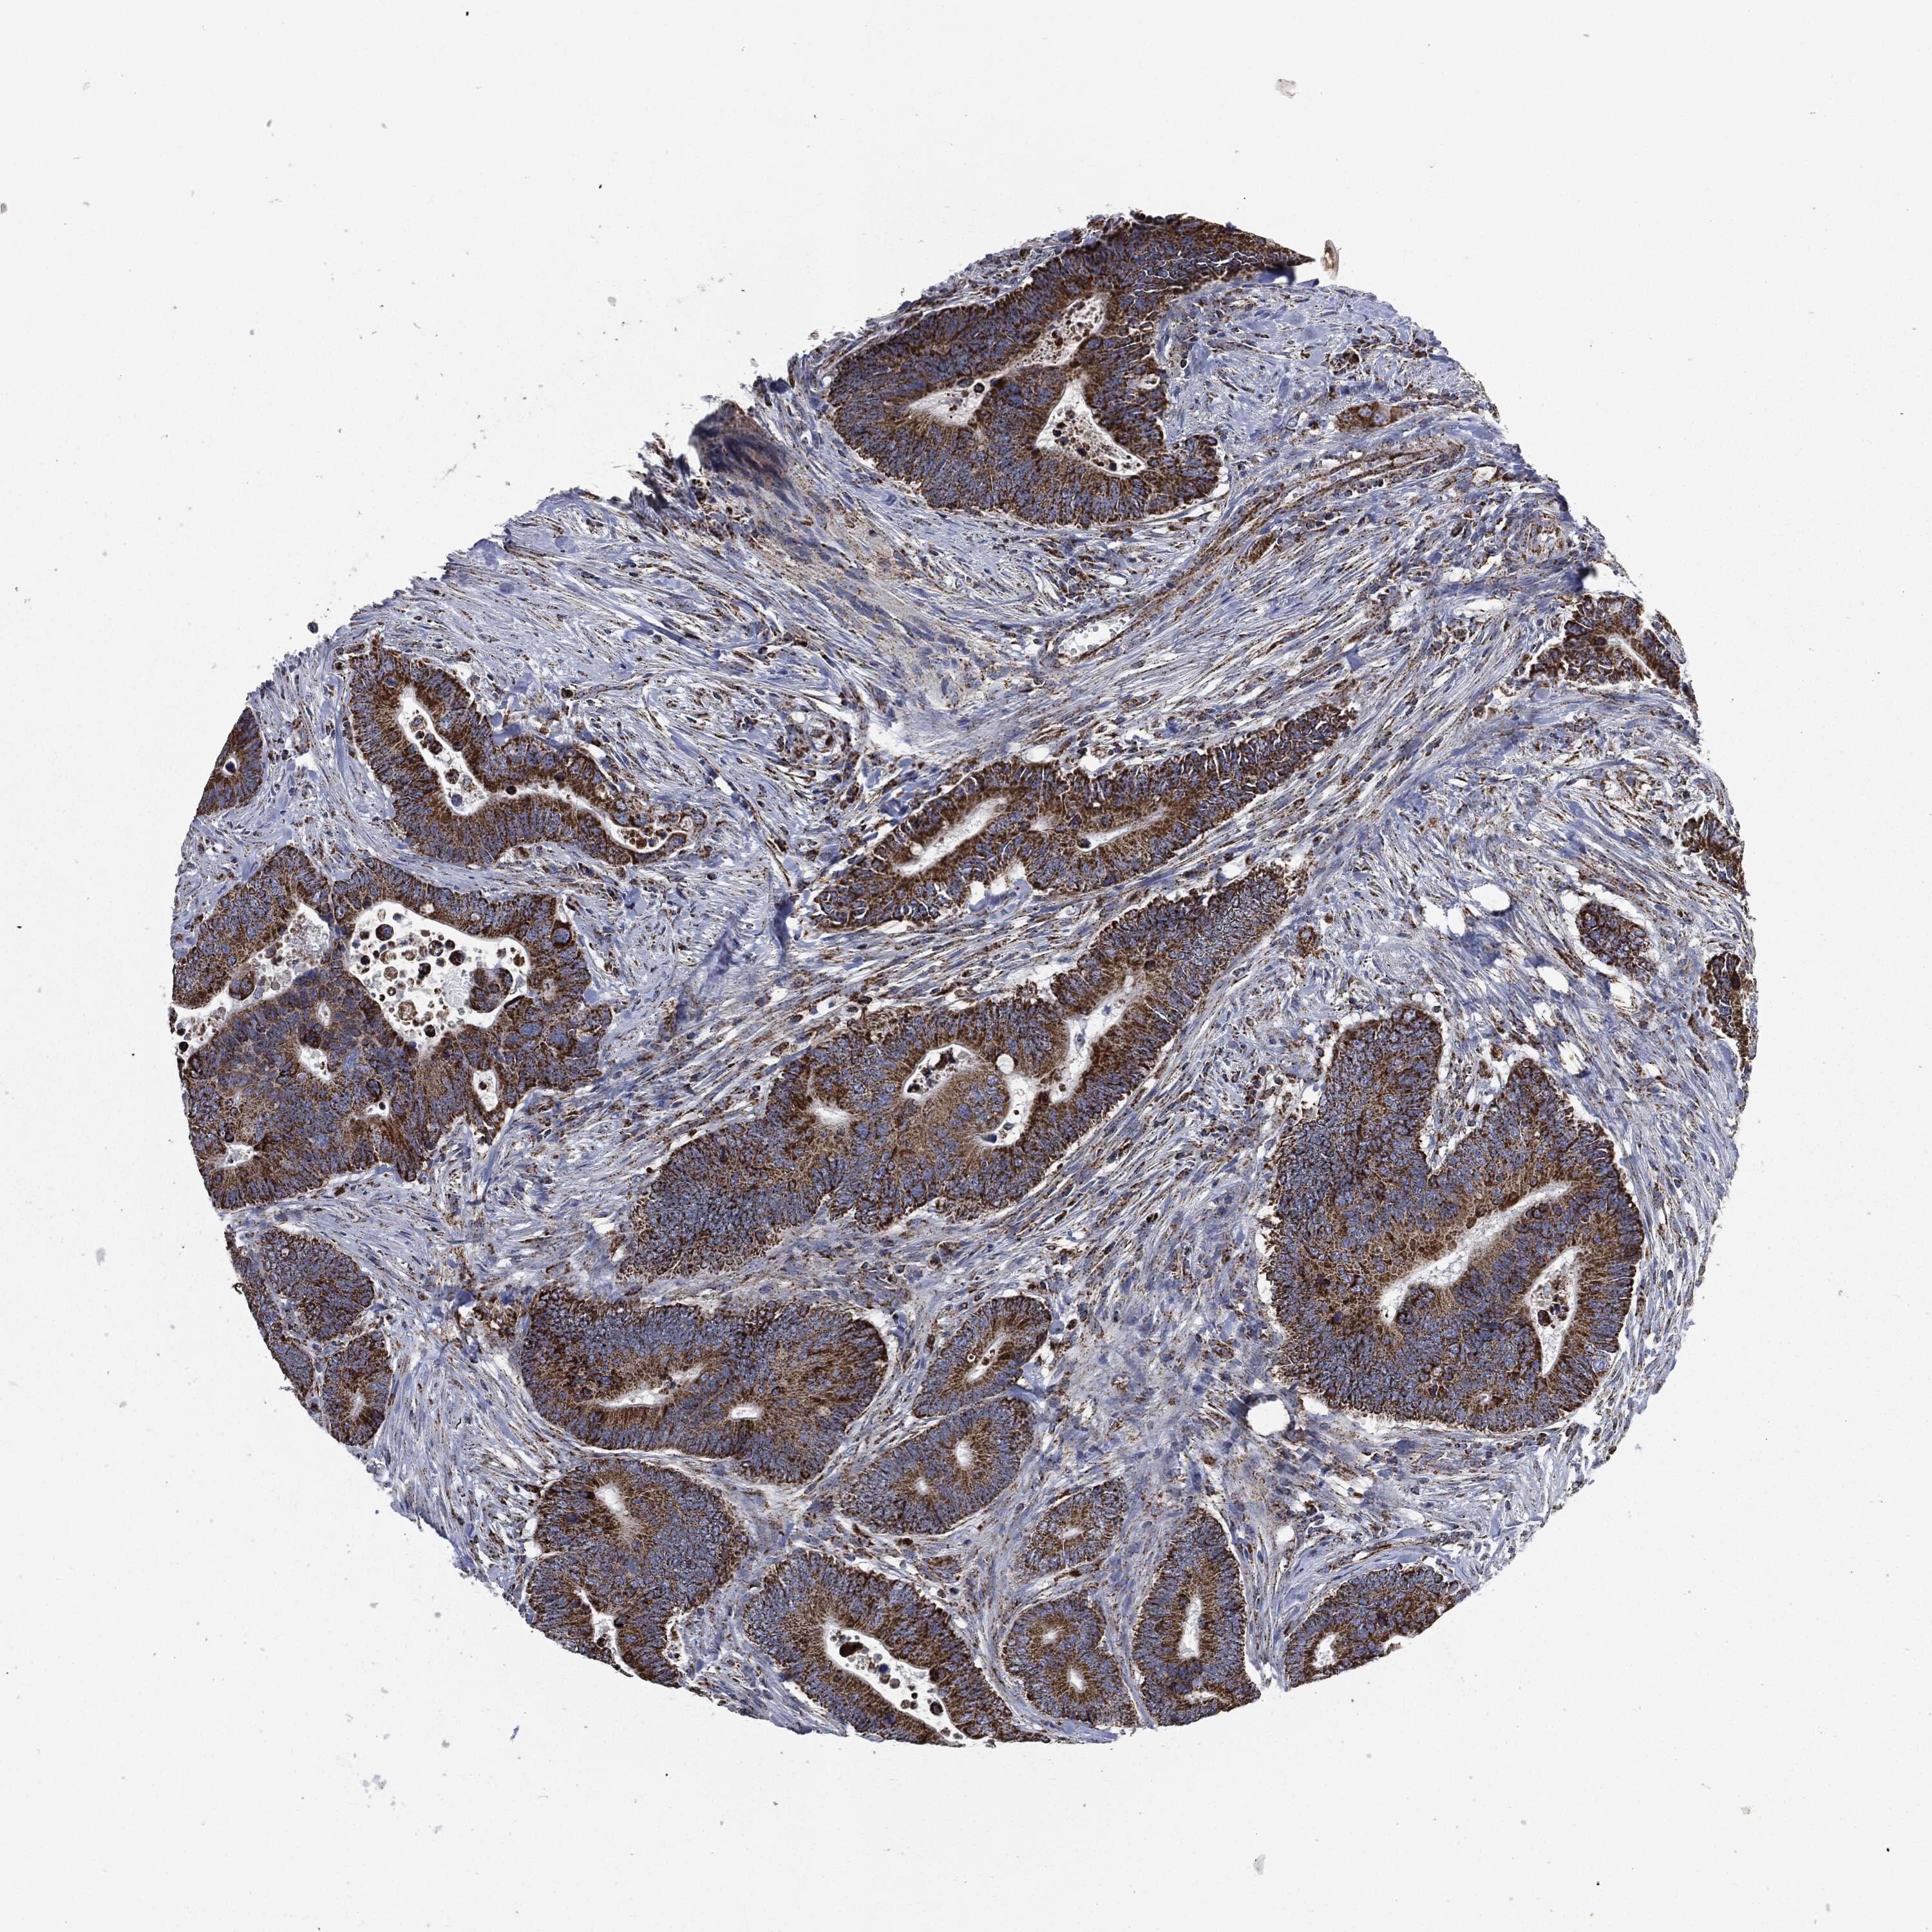

CANCER COLORECTAL CANCER Show tissue menu

Colorectal cancer

Human cancer

Colon adenocarcinoma